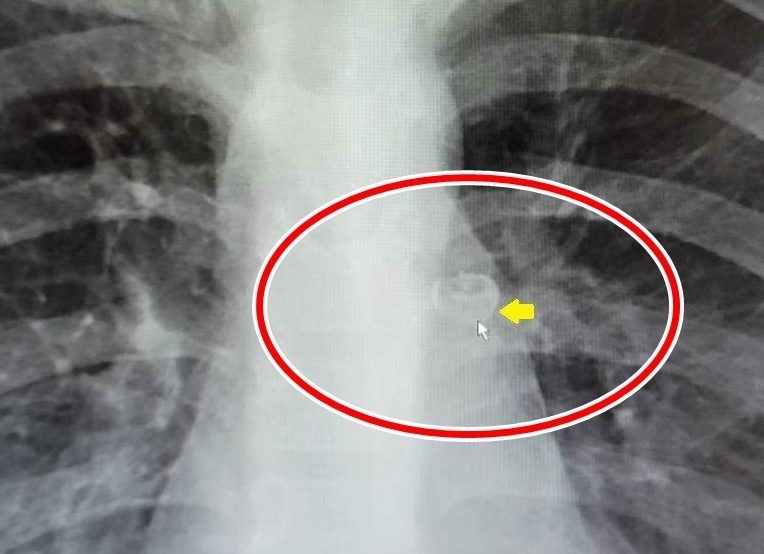

대만에서 11세 어린이가 집에서 어금니를 뽑다 삼켰는데, 이 어금니가 기관지 안에서 발견됐다. 자료 : 대만 타이베이 츠지병원

기침 증상이 완화되지 않자 홍군은 이튿날 타이베이 츠지병원 응급실을 찾았다. 병원에서 흉부 엑스레이를 촬영한 결과, 홍군의 왼쪽 기관지에 희미하지만 또렷한 형태의 어금니가 발견됐다.

홍군을 진료한 의료진은 홍군을 흉부외과로 보냈고, 의사는 기관지 내시경 검사를 통해 어금니의 정확한 위치를 파악했다.

이어 홍군에게 전신 마취를 한 뒤 옆으로 눕힌 채 등을 두드려 기관지에 박혀있는 어금니가 떨어지도록 했고, 소아용 기관지 내시경을 통해 어금니를 빼냈다.

“아이 몸부림에 어금니가 후두로 들어가”병원 측은 지난 10일 홍군의 흉부 엑스레이와 기관지 내시경으로 촬영한 사진 등과 함께 이같은 사례를 공개했다. 이어 “입에서 사라진 모든 것이 뱃속으로 들어가는 게 아니며, 자신도 모르는 사이에 기관지로 들어갈 수 있으니 주의해야 한다”고 강조했다.